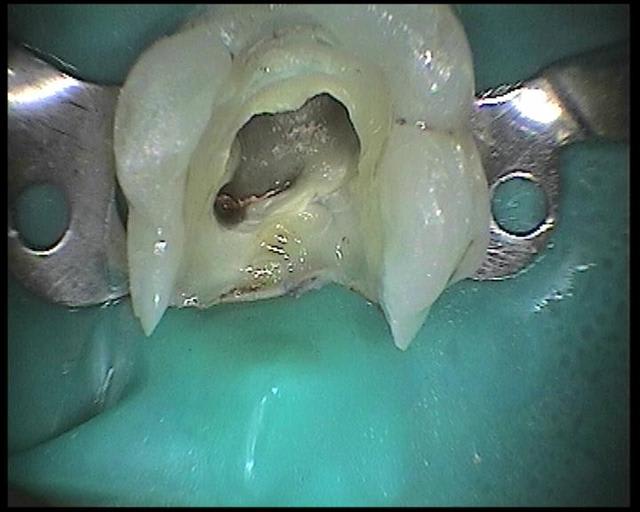

voici les images prises avec la sopro 595

Images en vrac de sopro 595